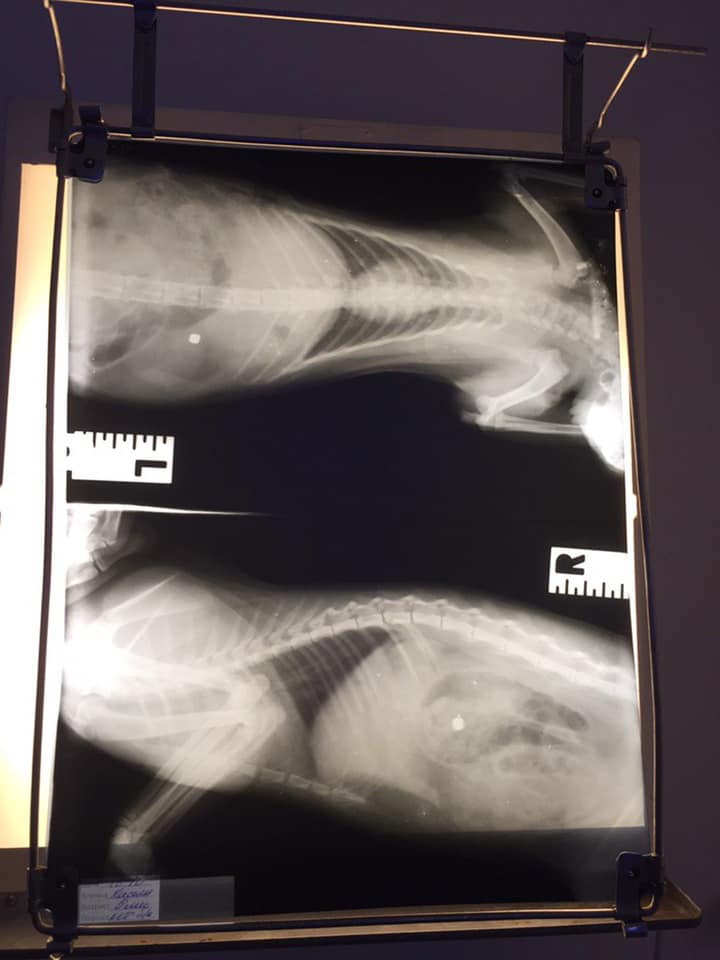

Она забрала его и отвезла в ветклинику, где ему сделали рентген. В заключении врача говорится, что кота ранили из пневматической винтовки. В результате этого у животного была кровь в брюшной полости, разрыв печени, перфорация кишечника, ушиб левой почки.

Рентген / фото: fb Яна ЧайкаРентген / фото: fb Яна Чайка